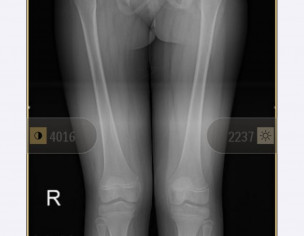

My daughter is diagnosed with hip dysplasia at age of 8.8 years. Doctor is saying for surgery immediately but we got another opinion and that surgeon is saying that there is no success rate of surgery right now. You have to wait once she grow up n then we will go for hip replacement. While the other doctor is saying that surgery is must. We need an opinion on it. Xrays are attached

she definitely need surgery to keep the head at level of socket. you should consult DR. CHIRAGH at GHURKI TRUST HOSPITAL, LAHORE. He is very experienced and expert for this disease.

it needs operation as soon as possible.

Surgery at present at 9yrs of age won't result good results. And re-dislocation may occur soon after surgery. Wait for maturity and then go for translational osteotony/replacement surgery.

Salam, She needs to get MRI of hip joint to measure angles related to hip dysplasia and clinical exam as well before deciding surgery. Thanks